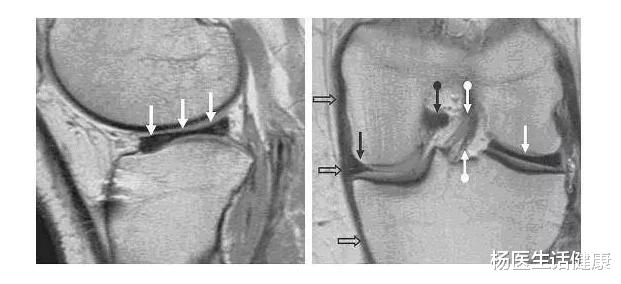

当我问及患者的病因症状功能时 , 他言及自己是运动爱好者 , 喜欢跑步、上健身房 , 关节不肿 , 走平路几乎无妨碍 , 下蹲不能到底 , 上下台阶不敢用力 , 偶尔打软腿 , 并无关节交锁表现 , 关节屈伸有弹响 。 症状出现一年 , 吃氨糖数月 , 打玻璃酸钠一疗程 , 其它贴膏药理疗等亦间断进行 , 症状有所缓解 。

由此 , 我便告诉他半月板损伤只是表面的磨损 , 虽然显示三度 , 但与你疼痛没有关联 , 你的疼痛是因为运动过度劳损所致韧带肌肉炎症而已!故保守疗法治疗即可 , 目的即消除炎症 , 康复锻炼以改善功能 , 以后运动量酌减即可 。

哪承想 , 其问出一句:我半月板三度损伤怎么办?那没关系啊 , 是正常的退变啊?其又追问:我感觉我的疼痛是半月板三度损伤所致 , 我们还是应该相信科学!